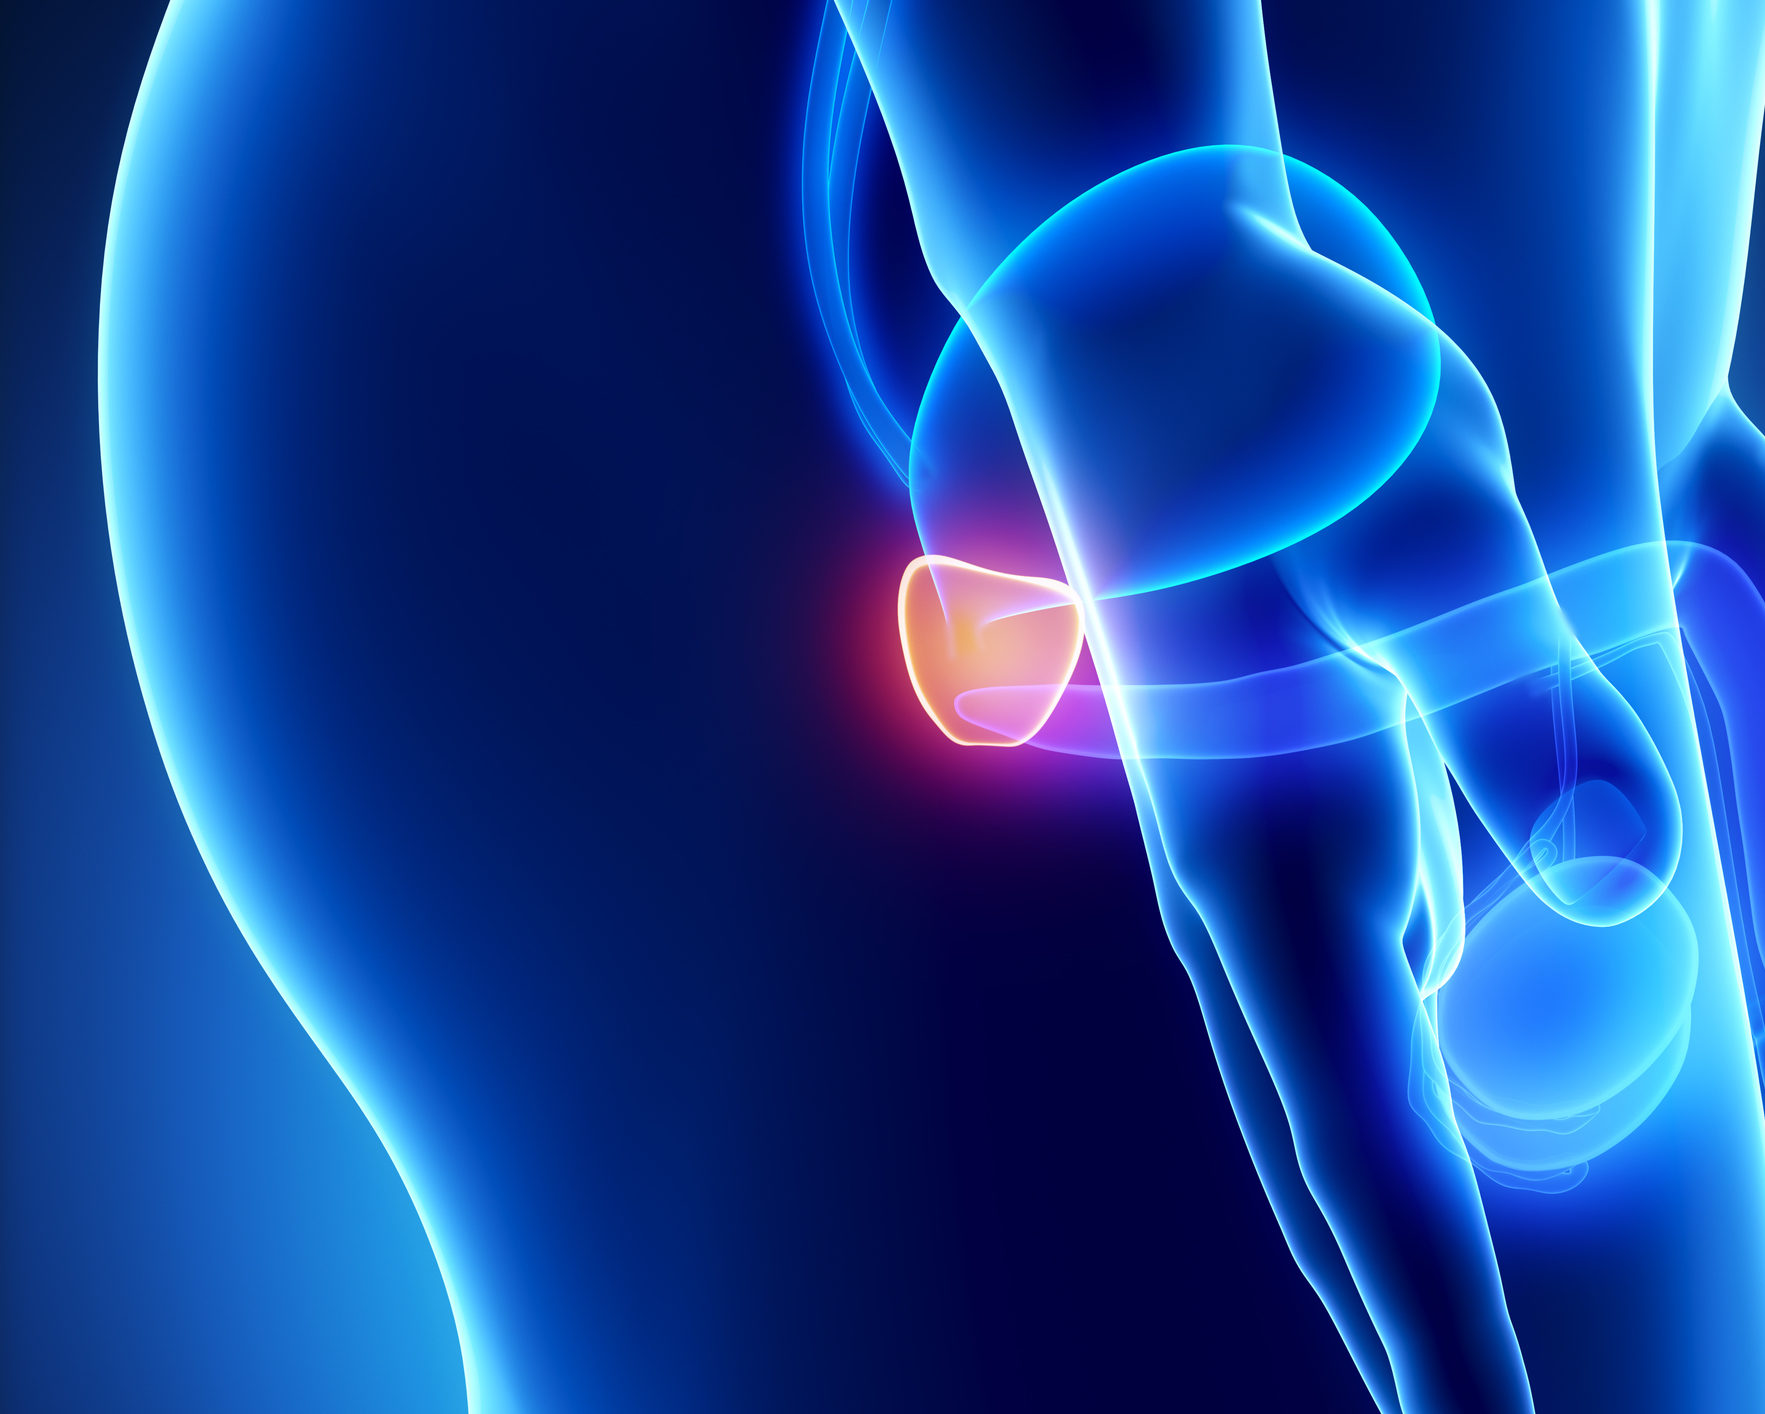

Prostatitis

Prostatitis is inflammation of the prostate, often causing pelvic discomfort, pain during urination, or difficulty urinating. It can be acute or chronic, and treatment may include antibiotics, anti-inflammatory medication, and supportive care.